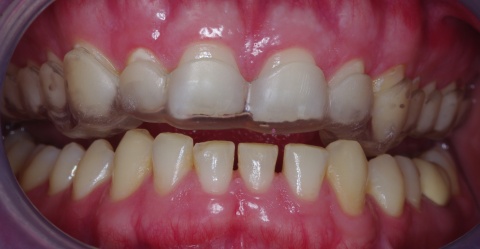

Eingliederung einer Kunststoff-Relaxationsschiene (Interceptor) im Oberkiefer mit gleichzeitigen Kontakten regio 13/14 sowie 23/24 zur Eckzahnführung bei Protrusion und Laterotrusion. (Abb. 1)

Zahnhartsubstanzdefekte von mehr als 50 % der Kronenlänge verursachen häufig kostenintensive prothetische Folgekosten bei geringer Haltbarkeit dieser Versorgungen (Wetselaar et al. 2009). Sichtbarer Verlust an Zahnhartsubstanz, ohne Kariesursache („Toothwear“) als Attrition durch Bruxismus verursacht, kann durch Erosion von Säure (Nahrung, Erbrechen) und Abrasion (meist auf die Anwendung von groben Zahnpasten und aggressiven Zahnputztechniken zurückzuführen) verstärkt werden. Zur Quantifizierung der verlorenen Zahnhartsubstanz erfolgte die Bestimmung des Tooth Wear Index an Ober- und Unterkiefermodellen (mod. TWI 0 – 7 n. Wetselaar et al. 2009).

CMD und Bruxismus sind unterschiedliche Krankheitsbilder. Der Vorhersagewert von vorhandenen Attritionen durch Zahnknirschen für eine PTBS-Entwicklung wurde in einem retrospektiven wehrmedizinischen Sonderforschungsprojekt (12K1-S-80 1414) durch unsere Arbeitsgruppe eruiert. Die vorgelegte Untersuchung belegt, dass an PTBS erkrankte Soldaten aus Kriegseinsätzen signifikant häufiger schmerzhafte orofaziale Funktionsstörungen (bei 80 % konnte ein Kiefergelenksknacken beobachtet werden, 100 % litten unter schmerzhaften Muskelbefunden) entwickeln. Hierbei ergaben sich hohe Korrelationen für chronische Schmerzwerte der Kiefer- und Gesichtsmuskulatur (GCS-Fragebogen, DentaConcept), eingeschränkter Mundöffnung (31,4 ± 8,0 mm), Stressparametern (DASS-Fragebogen, DentaConcept) und ausgeprägten Zahnattritionen (> 30 % der natürlichen Zahnkronenlänge) mit der PTBS-Entwicklung im Vergleich zu einer Kontrollgruppe die über vergleichbare Auslandseinsatzbelastung, Alter, Geschlecht und Zahnzahl verfügte. 80 % der PTBS-Patienten hatten vor der stationären Aufnahme neben einer Blut- und Verletzungsphobie ebenfalls eine Zahnbehandlungsphobie entwickelt und über mehr als zwei Jahre keinen Zahnarzt für Behandlungs- oder Präventionsmaßnahmen aufgesucht.